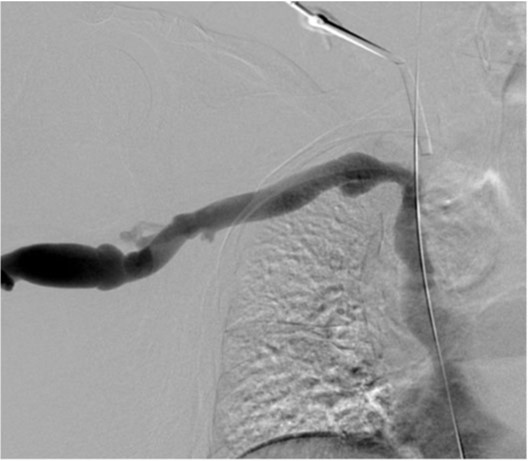

Fig. 2.

Fig 2. Venogramshows short segmental occlusion of right brachiocephalic vein (long arrow) and vascular sheath (short arrow) within SVC which was inserted via right common femoral vein.

초음파 유도 하에 우측 팔의 동정맥루 graft를 천자한 후 정맥조영술을 시행하여 우측 상완두정맥의 폐색을 확인함(Fig. 1). 5Fr Cobra 카테터(Cook, Bloomington, IN, USA)와 친수성 0.035 inch 유도철사(Terumo, Tokyo, Japan)로 폐색부위의 통과를 시도하였으나 실패함. 우측 대퇴정맥을 천자하고9Fr 65cm sheath (Arrow, Deutschland, Erding, Germany)를 상대정맥까지 진입시킨 후 5Fr Davis 카테터를 통해 약 2cm 길이의 상완두정맥 폐색 부위를 확인함(Fig. 2). Davis 카테터와유도철사로 상대정맥에서 우측 상완두정맥으로 통과를 시도함. 유도철사의 soft tip 부분으로 시도하였을 때 통과가 되지 않아서 반대쪽 hard tip 부분으로도 통과를 시도 하였으나 실패함(Fig.3). 유도 철사의 soft tip 과 hard tip 양쪽 모두 사용 하여 통과를 시도하였으나 막힌 부위의 위쪽 부분은 앞쪽(anterior side of the body) 을 향하고 있고 아래쪽 부분은 뒤쪽(posterior side of the body)를 향하고 있어서 천자 방향을 맞추기 어려웠음(Fig. 3). 우측 내경정맥을 천자하고 5Fr sheath를 삽입함. Sheath를 통해서 5FrKumpe 카테터와 0.035 inch 유도철사로 위에서 아래 방향으로 폐색부위 통과를 시도함. Hard tip으로 시술 도중 폐색혈관 주위로 유도 철사가 천자되어서 조영제의 누출이 있었으나 천자부위 주에 국한되어 있었고 임상적으로 문제 있는 혈류역학적 변화는 오지 않았음. Kumpe 카테터와 유도철사로는 천자 방향을 맞추기가 어려워서TIPS set (Cook, Bjaeverskov, Denmark)를 사용하기로 함. 천자된내 경정맥에 10Fr introducer sheath를 삽입하고 20G Colapinto needle을 폐색부위까지 진입시킴. 양쪽에서 정맥 조영술을 시행하여 폐색된 부위의 위치와 길이를 여러 각도에서 정확히 파악한 후, 폐색 부위를 천자함(Fig. 4). 천자 후 Colapinto needle을 통해 유도철사를 상대정맥에 진입시킴. 대퇴동맥을 통하여 삽입된 snare 카테터(ev3, Plymouth, MA, USA)를 이용하여 대퇴정맥 밖으로 유도철사를 빼냄(through and through technique)(Fig 5). 유도 철사만 통과된 상태에서 천자부 주위에 여러번의 천자로 인한 조영제 누출이 있었으나 주출된 조영제의 양이 적었으며 천자부 주위에 국한되어 있었음. Tractogram시행시 조영제의 누출은 보이지 않아서 유도 철사 주위에 국한 되어 있어서 풍선확장술을 시행 하기로 함(Fig. 6).대퇴 정맥을 통해 유도철사를 0.035 inch Amplatz wire(Cook, Bjaeverskov, Denmark)로 교체하여 내경정맥까지 진입시킨 후 풍선카테터 (Bard, NJ, US)를 삽입함.천자된 통로를 따라 직경 6 mm에서부터 16 mm까지의 풍선카테터로 차례대로 풍선확장술을 시행함(Fig. 7). 시술 후 정맥조영술에서 폐색부위는 개통되어 원활한 혈류를 보였음(Fig. 8). 시술 후에 오른쪽 팔의 종창은 호전됨.